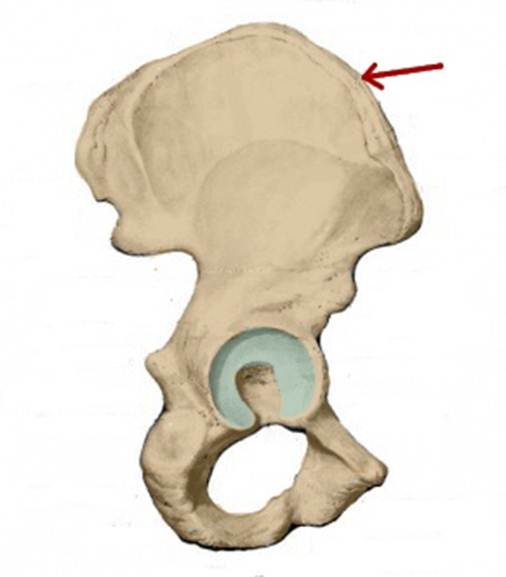

I:

S: Стрелка указывает на os pubis (латинский язык).

I:

S: Стрелка указывает на os ilium (латинский язык).

I:

S: Стрелка указывает на os ischii (латинский язык).

S: Стрелка указывает на ramus superior ossis pubis

S: Стрелка указывает на ramus inferior ossis pubis

S: Стрелка указывает на ramus ossis ischii

S: Стрелка указывает на foramen obturatum (латинский язык).

S: Стрелка указывает на tuberculum pubicum

S: Стрелка указывает на facies lunata (латинский язык).

S: Стрелка указывает на spina iliaca anterior inferior

S: Стрелка указывает на spina iliaca anterior superior

S: Стрелка указывает на eminentia iliopubica

I:S: Стрелка указывает на spina iliaca anterior superior